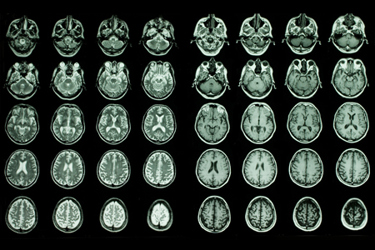

Despite decades of progress in oncology, patients diagnosed with cancers of the central nervous system (CNS) continue to face limited treatment options and poor outcomes. Primary brain tumors and metastatic disease to the brain and leptomeninges remain among the most challenging conditions in medicine, largely due to biological complexity, treatment resistance, and the difficulty of delivering therapies safely and effectively to the CNS.

Unlike tumors in many other parts of the body, CNS cancers present a dual challenge: eradicating malignant cells while preserving critical neurological function. The blood–brain barrier limits the penetration of many systemic therapies, while conventional treatments, such as surgery and external beam radiation, may fall short for infiltrative or disseminated disease.

In conditions such as gliomas or leptomeningeal metastases, cancer cells can spread diffusely throughout the CNS, making focal treatments insufficient. Systemic chemotherapies may struggle to reach therapeutic concentrations at the site of disease, and cumulative toxicity often limits dosing.